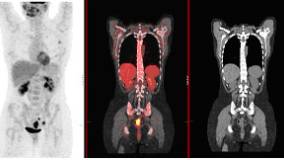

Clinical PET/CT

Establishing a clinical protocolClinical applicationsArtefacts and normal variantsClinical Imaging